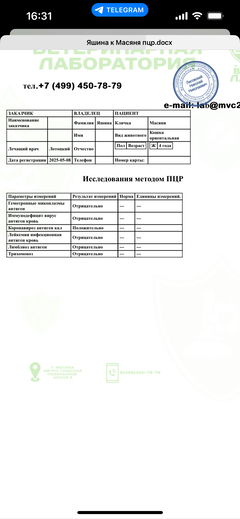

Была куплена в питомнике взрослой. У Масяни начались проблемы с кишечником и она стала подтекать и все пачкать. Надо отдать должное хозяевам - ее обследовали вдоль и поперек - как говорили местные врачи, сдавали много анализов но диагноза так и не поставили.

И проблема никуда не ушла 😔

Ярко выраженная болезненность в области крестца, на обезболе полегче. По результатам приема невролога проведена миелография - множественная компрессия, возможно опухоль, возможно грыжа, нужно удалять...